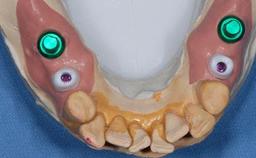

Type of Implants Two-Piece

Attachment Two-Piece

Abutment Type Customized

Retention Cemented, with meso-structure Cemented, with meso-structure